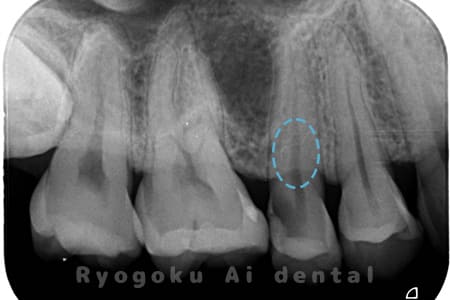

Case02

-

- 原因

- C3、インレー不適合

- 治療期間

- 1ヶ月

- 治療内容

- 断髄治療

- 治療費用

- 66,000円

虫歯の治療と銀歯のやり直しを希望され、銀歯を外したところ、虫歯が大きく、神経の処置が必要と判断。患者様と相談し、神経を残す断髄治療となったケース。

<リスク・副作用>

術後は痛み、腫れ、痺れなどの副作用が生じる場合があります。症状が再発する可能性があります。その場合は抜髄する必要があります。